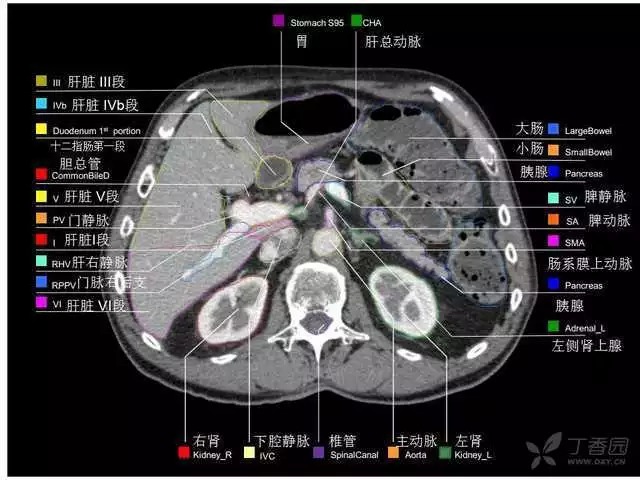

腹部肝脏高清CT断层的图谱

全腹部高清CT图谱,淋巴结彩色图谱,血管解剖图谱大汇总!

超声肝脏分叶及分段

肝脏分段和基本解剖学标志